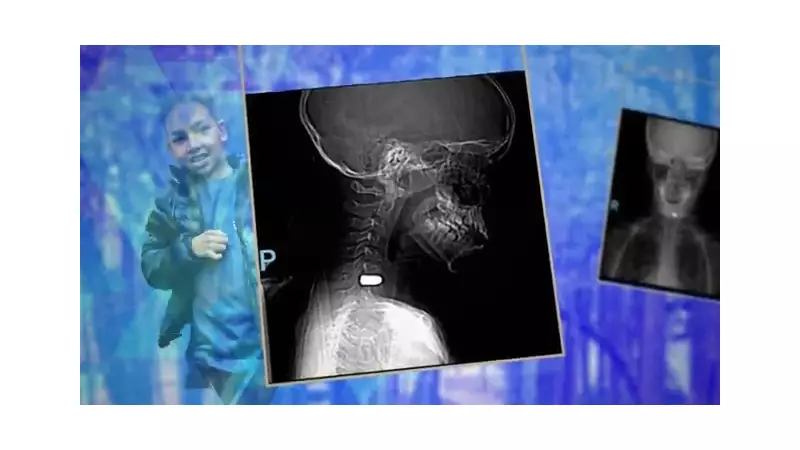

Mateus, um menino de apenas 10 anos, vítima de uma bala perdida durante as comemorações do réveillon na zona leste de São Paulo, está surpreendendo familiares e médicos com sua notável recuperação. Apesar de ainda ter o projétil alojado próximo à coluna vertebral, o garoto já voltou a caminhar, correr e realizar atividades cotidianas, em um processo que a família classifica como verdadeiro milagre.

O garoto passou nove dias hospitalizado, sendo seis deles na Unidade de Terapia Intensiva. Após receber alta, enfrentou desafios significativos: não conseguia andar, havia perdido os movimentos do lado direito do corpo - incluindo a mão dominante, já que é destro - e precisou utilizar cadeira de rodas temporariamente. "Eu pensei que eu não ia voltar a andar", confessa o próprio Mateus sobre esse período difícil.

Os médicos explicaram que a bala passou extremamente perto da medula espinhal, causando inflamação significativa, mas felizmente não chegou a seccionar o nervo. O projétil permanece alojado em uma parte óssea da região, decisão médica que considerou a remoção cirúrgica mais arriscada do que mantê-lo no local.